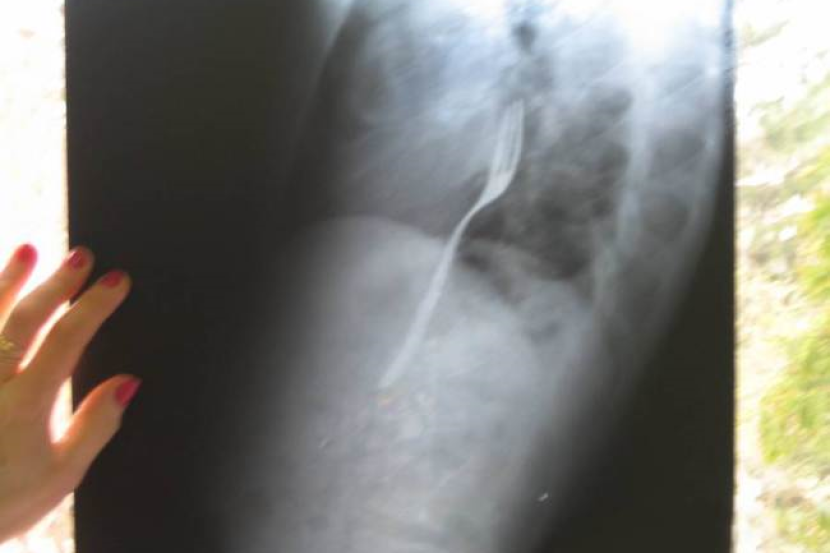

Doktor yang membuat imbasan x kemudiannya terkejut apabila mendapati garpu berada di dalam usuS Calincescu.

Hasil desakan doktor, Calincescu kemudian mengaku, "Saya bertaruh dengan kawan bahawa saya boleh menelan garpu tanpa sebarang kecederaan ke atas diri."